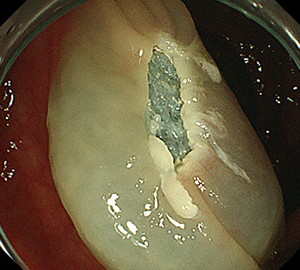

内視鏡的粘膜切除術(EMR)

外来にて切除することの出来ない、比較的大きめの大腸ポリープや平坦な病変などの切除の際に行います。

| 1:ポリープを見つけ、NBI併用拡大観察をした後、 | 2:ポリープ直下の粘膜下層に局注液を注入し盛り上げます。 | |

| 3:ポリープをスネアに通し、周囲の正常粘膜を入れて病変を絞扼 | 4:電気を流してして切除します。 | |